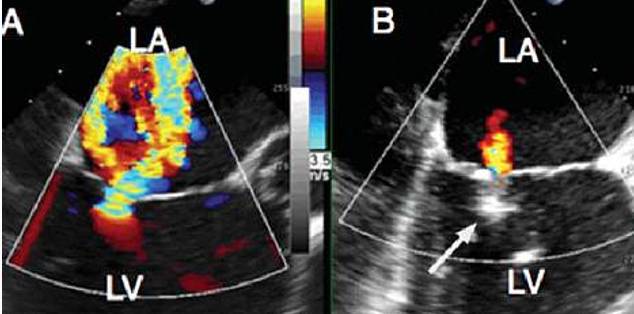

超声评价

超声提示严重MR

释放Clip后反流明显减轻

三维超声下显示二尖瓣呈双孔